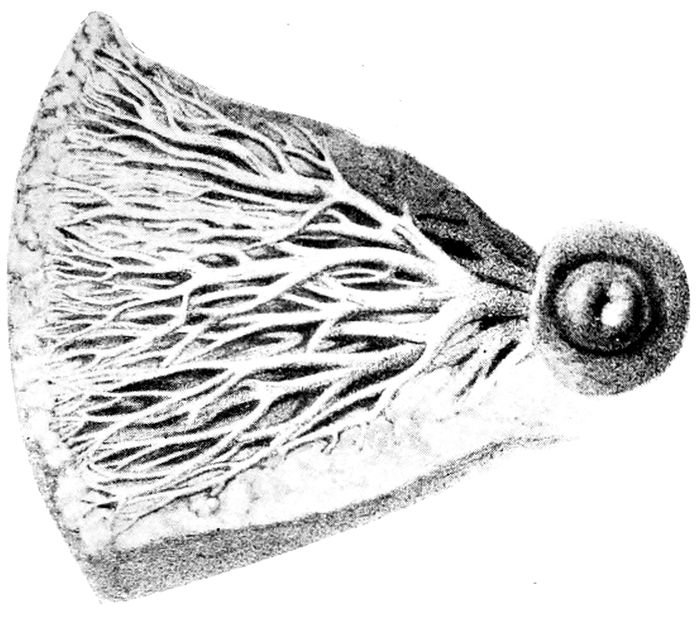

Fig. 8 A.—The excreting ducts of the mammary gland. (Lenoir and Tarnier.)

Fig. 8 B.—Lobules and duct of the mammary gland. (Lenoir and Tarnier.)

The Mammary Glands.—The mammary glands are

The breast is made up of fifteen or twenty lobes, each

of which, like a bunch of grapes, clusters about and

discharges into a single tube which, in turn, leads to

the nipple. The area between the lobes is filled with

fat and connective tissue.